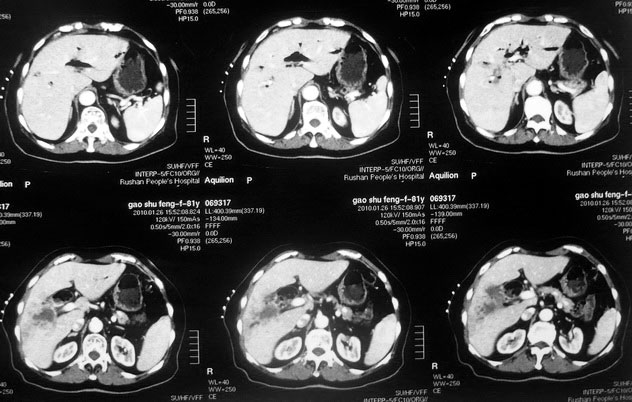

肝癌合并肝脓肿

女,80岁既往有胆系手术史。近2月出现食欲不振,近20天出现畏寒发热,体重约下降10kg,体温一般在38℃左右。血常规wbc正常,中性比例88%,cea 10.3,afp、ca199均正常。做过一次肝穿,抽出约3ml仿佛脓性液体。这是她的增强ct扫描,请大家帮帮忙。另外想问问肝脓肿和胆管细胞癌的ct表现有什么区别。谢谢了。

【湘江一滴】化脓性胆囊炎及胆管炎,肝内胆管积气、积液、扩张;胆囊壁增厚、强化;胆周积液。未见肝内占位征象。

【shuiyuan】化脓性胆囊炎及胆管炎,肝内胆管积气、积液、扩张;胆囊壁增厚、强化;胆周积液.

肝脓肿动脉期呈明显环形强化或蜂窝状强化,胆管细胞癌动脉期强化不明显,且伴肝内胆管扩张。

【zenxisengming 】肝内胆管扩张积气,胆囊比环形增厚,胆囊周围渗出,未见占位性病变,应该是胆道化脓性感染

【sunbin】肝内见多个气体密度影伴气液面,胆囊壁增厚,胆囊周围低密度环绕,未见强化,支持化脓性胆管炎、胆囊炎。

最近复查ct,做了第二次穿刺抽脓,顺便做了涂片病理活检,结果找到恶性肿瘤细胞,诊断肝癌合并肝脓肿。看来大家都走眼了啊。